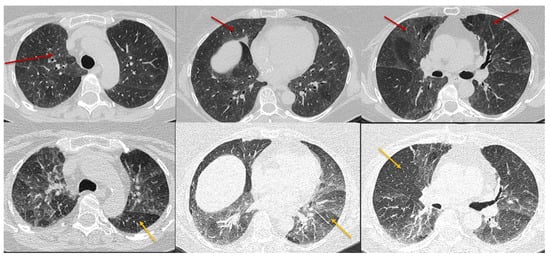

Three categories of NFHP (Table 3, Figure 8) and FHP (Table 4, Figure 9, Figure 10, Figure 11 and Figure 12) have been described.

Figure 8. Typical non-fibrotic HP. Inspiratory phase CT (top row) shows ground glass opacities (red arrows) and expiratory phase CT (bottom row) shows air trapping (yellow arrows). Note the diffuse axial and craniocaudal distribution.